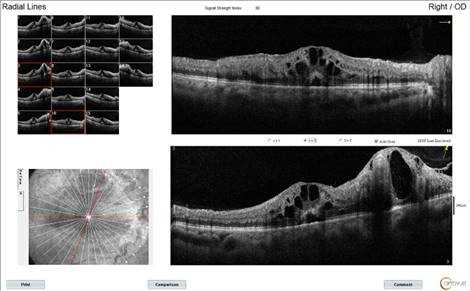

При проведении оптической когерентной томографии в макулярной области и в области сосудистых петель выявлены следующие изменения: диффузное утолщение с гипорефлективными пространствами в наружных слоях сетчатки; небольшое количество субретинальной жидкости; в наружных слоях сетчатки видны кистозные изменения, захватывающие несколько ее слоев (рис. 2).

Рис. 2. Данные оптической когерентной томографии, выполненной через макулу, до лечения: отмечается утолщение интраретинальной области; кистозные изменения захватывают несколько ее слоев в самой макуле и в зоне патологически измененных сосудов

По данным спектральной ОКТ отмечается явная положительная динамика: снижение толщины внутренних слоев сетчатки, уменьшение количества интраретинальных кист, восстановление фовеолярного профиля. На фоне проводимой терапии отмечается уменьшение «напряжения» в аномальных сосудистых петлях, их расположение стало более плоским за счет уменьшения отека подлежащей сетчатки. Сохраняются локальный тракционный отек сетчатки за счет патологически измененных сосудов и натяжения со стороны стекловидного тела, уплотнение гиалоидной мембраны, выраженные неровности ретинальной поверхности (рис. 4).

Рис. 4. Данные оптической когерентной томографии после лечения: регресс отека внутренних слоев сетчатки, уменьшение количества интраретинальных кист, восстановление фовеолярного профиля